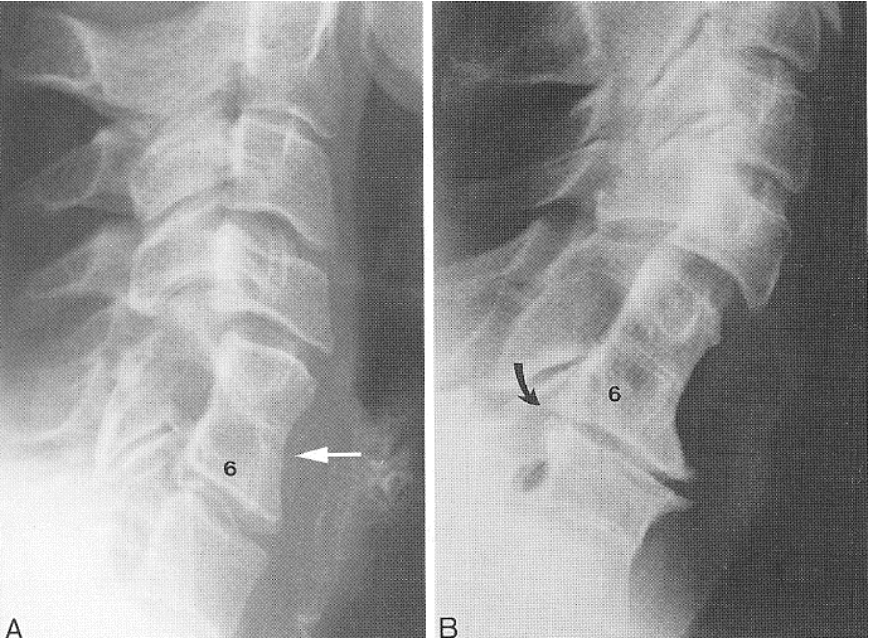

What fusion has these radiographic features? -2+ congenital block vertebra in the cervical or upper thoracic region OR a congenital block with 3+ segments involved -sprengel's deformity 25% of the time -omovertebral bone 30-40% of the time

Klippel-Feil syndrome

What is this?

Klippel-Feil syndrome (congenital block at C2/C3 and C6/C7)